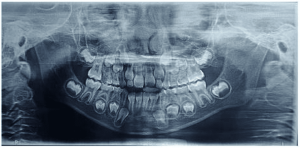

A 49-year-old female patient attended the prosthesis clinic at Nilton Lins University, mentioning dissatisfaction with her total obturator prosthesis, because she had a “broken front tooth” and the prosthesis was “falling”, emphasizing the desire to maintain the shape of the same. In the anamnesis reported that previously in 2012 he was diagnosed with mucoepidermoid carcinoma of intermediate degree in the palate (Appendix 1) and in 2013 after performing surgical removal and performing new tests, who did not indicate the presence of malignancy (Appendix 2), was attested as cured, besides being hypertensive and using the drugs losartan potassium 50 mg twice daily and levanlodipine besidate 2.5 mg once a day. No alterations were observed on extraoral clinical examination. In the intraoral clinical examination, there was absence of the upper arch teeth, bucosinusal communication and partial maxillary edge and in the lower region only the presence of teeth 31, 32, 33, 41, 42, 43, 44 and 45 (figures 1 and 2).

Figure 1: Surgical defect of the upper arch.